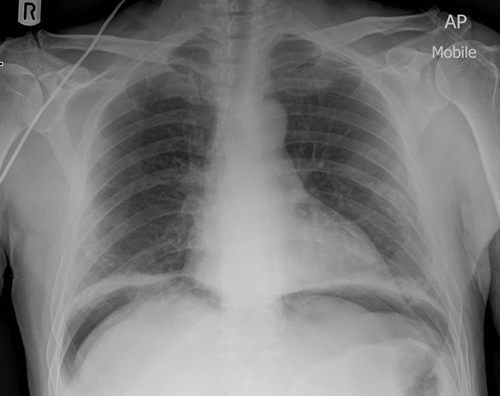

BHL

Sarcoidosis, malignancy, TB

Ask about joint pain, cough

Consolidation

opacification with air bronchograms

e.g cancer, pneumonia, haemorrhage, edema

Pneumothorax

Tension pneumothorax

Pleural effusion

Right Middle Lobe consolidation

Right upper lobe collapse

Hyperinflation

Heart Failure

(- prosthetic valves)

LVA

Pulmonary edema

+- pleural effusions

+- heart failure